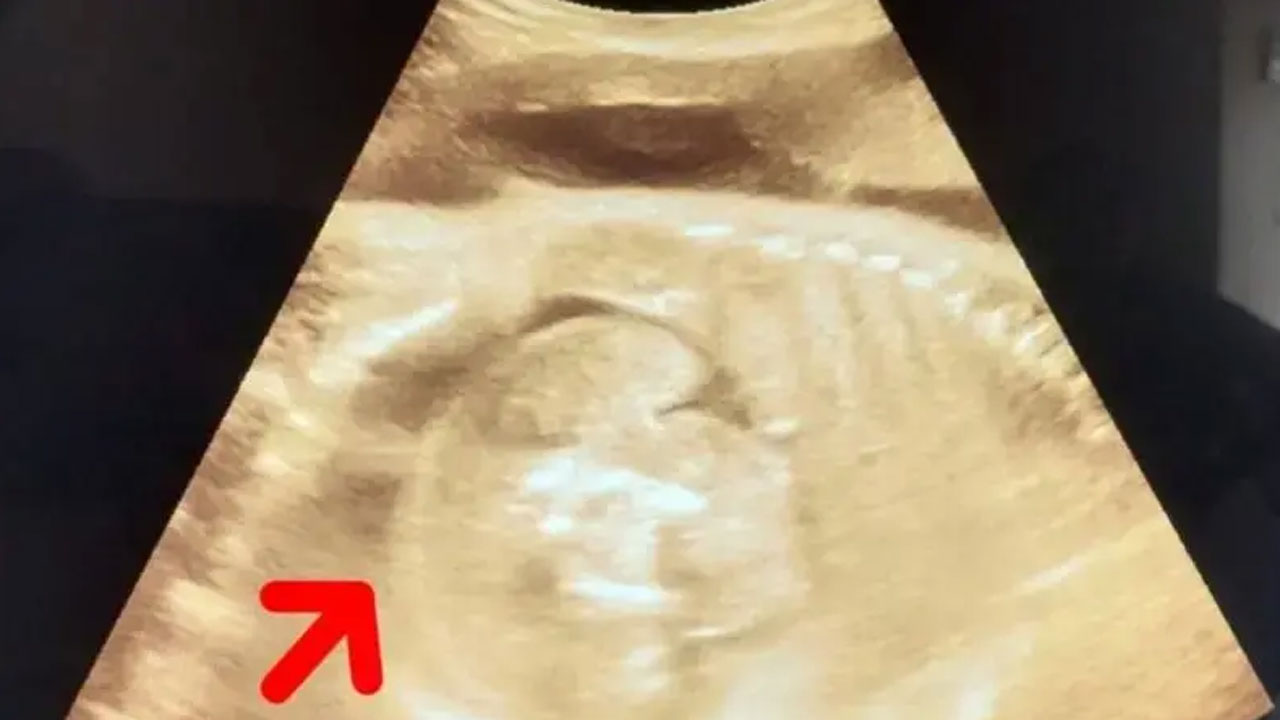

ভারতের মহারাষ্ট্রে এক নারীর গর্ভে থাকা শিশুর শরীরে আরও একটি ভ্রূণের সন্ধান পাওয়া গেছে। সম্প্রতি ওই নারী সোনোগ্রাফি করানোর জন্য হাসপাতালে যান। তখন চিকিৎসকরা এ বিষয়টি লক্ষ্য করেন।

জানা যায়, ৩২ বছরের ওই নারী তার গর্ভাবস্থার অষ্টম মাসে সোনোগ্রাফি করাতে গত বুধবার হাসপাতালে যান। তখন পরীক্ষা করে জানা যায়, ওই নারীর গর্ভে যেমন একটি শিশু রয়েছে, তেমনই ওই শিশুর গর্ভেও একটি ভ্রূণ রয়েছে। বিষয়টি সম্পর্কে নিশ্চিত হতে চিকিৎসক এবং বিশেষজ্ঞদের একটি টিম আরও একবার সোনোগ্রাফি করেন। তখনও গর্ভে থাকা শিশুটির গর্ভে একটি ভ্রূণ স্পষ্টভাবে দেখা যাচ্ছিল।

হাসপাতালের এক শল্যচিকিৎসক (সিভিল সার্জন) বলেছেন, সোনোগ্রাফি পরীক্ষার পর দেখা যায়, ওই নারীর গর্ভে একটি শিশু রয়েছে এবং শিশুটির গর্ভে আরও এক শিশু রয়েছে। তবে একে ঠিক শিশু বলা যাবে না, কারণ এটি ফিটাল মাস। এক অর্থে বলতে গেলে, এটি একটি মাংসের পিণ্ড।

বিষয়টিকে আরও বিশদে ব্যাখ্যা করে তিনি বলেন, ওই মাংসপিণ্ড আকারে বৃদ্ধি পাচ্ছে, কারণ সেখানে রক্ত সরবরাহ অব্যাহত রয়েছে। ডাক্তারি ভাষায় একে ফিটাস ইন ফেটু (ভ্রূণের অভ্যন্তরে ভ্রূণ) বলা হয়।